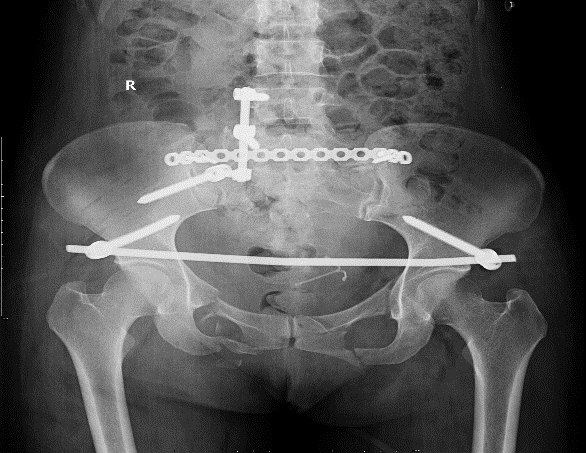

随后,骨科接诊后,经过充分的讨论及术前准备,骨科主任黄勇对张女士做了后路椎弓根螺钉及髂骨螺钉内固定术+后外侧植骨融合术+神经探查术+耻骨骨折切开复位内固定术。手术过程顺利,术中出血仅400ml,术后张女士转入了骨科术后监护病房。

患者术后骨盆平片